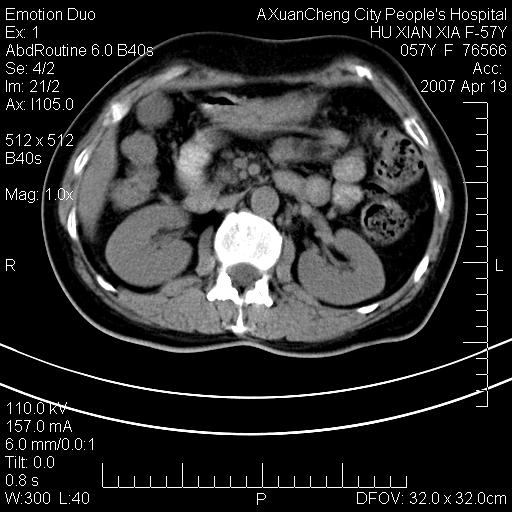

标题: CT7778:[原创]F,57Y腹痛待查,胸片提示肺部占位,应当很典型 [打印本页]

标题: CT7778:[原创]F,57Y腹痛待查,胸片提示肺部占位,应当很典型

胸片提示肺部占位

考虑:1、双侧肾上腺占位.2、肝左叶内侧段不规则低密度灶,建议强化扫描.

忽略了,只以为急腹症,应该支持肺癌肾上腺转移,肺癌患者20-30%发生肾上腺转移

双侧肾上腺增大,有分叶,密度均匀,考虑转移建议查原发灶

1.双侧肾上腺占位,转移首先考虑。

2.肝硬化,门静脉高压;肝左叶内侧段病灶建议增强。

3.12指肠水平段狭窄,建议行低张12指肠造影。

双侧肾上腺结节样肿块,结合肺部肿块,考虑肺癌肾上腺转移。

双侧肾上腺及腹膜后淋巴结增大,结合胸片提示肺部占位,考虑肺癌双侧肾上腺及腹膜后淋巴结转移.